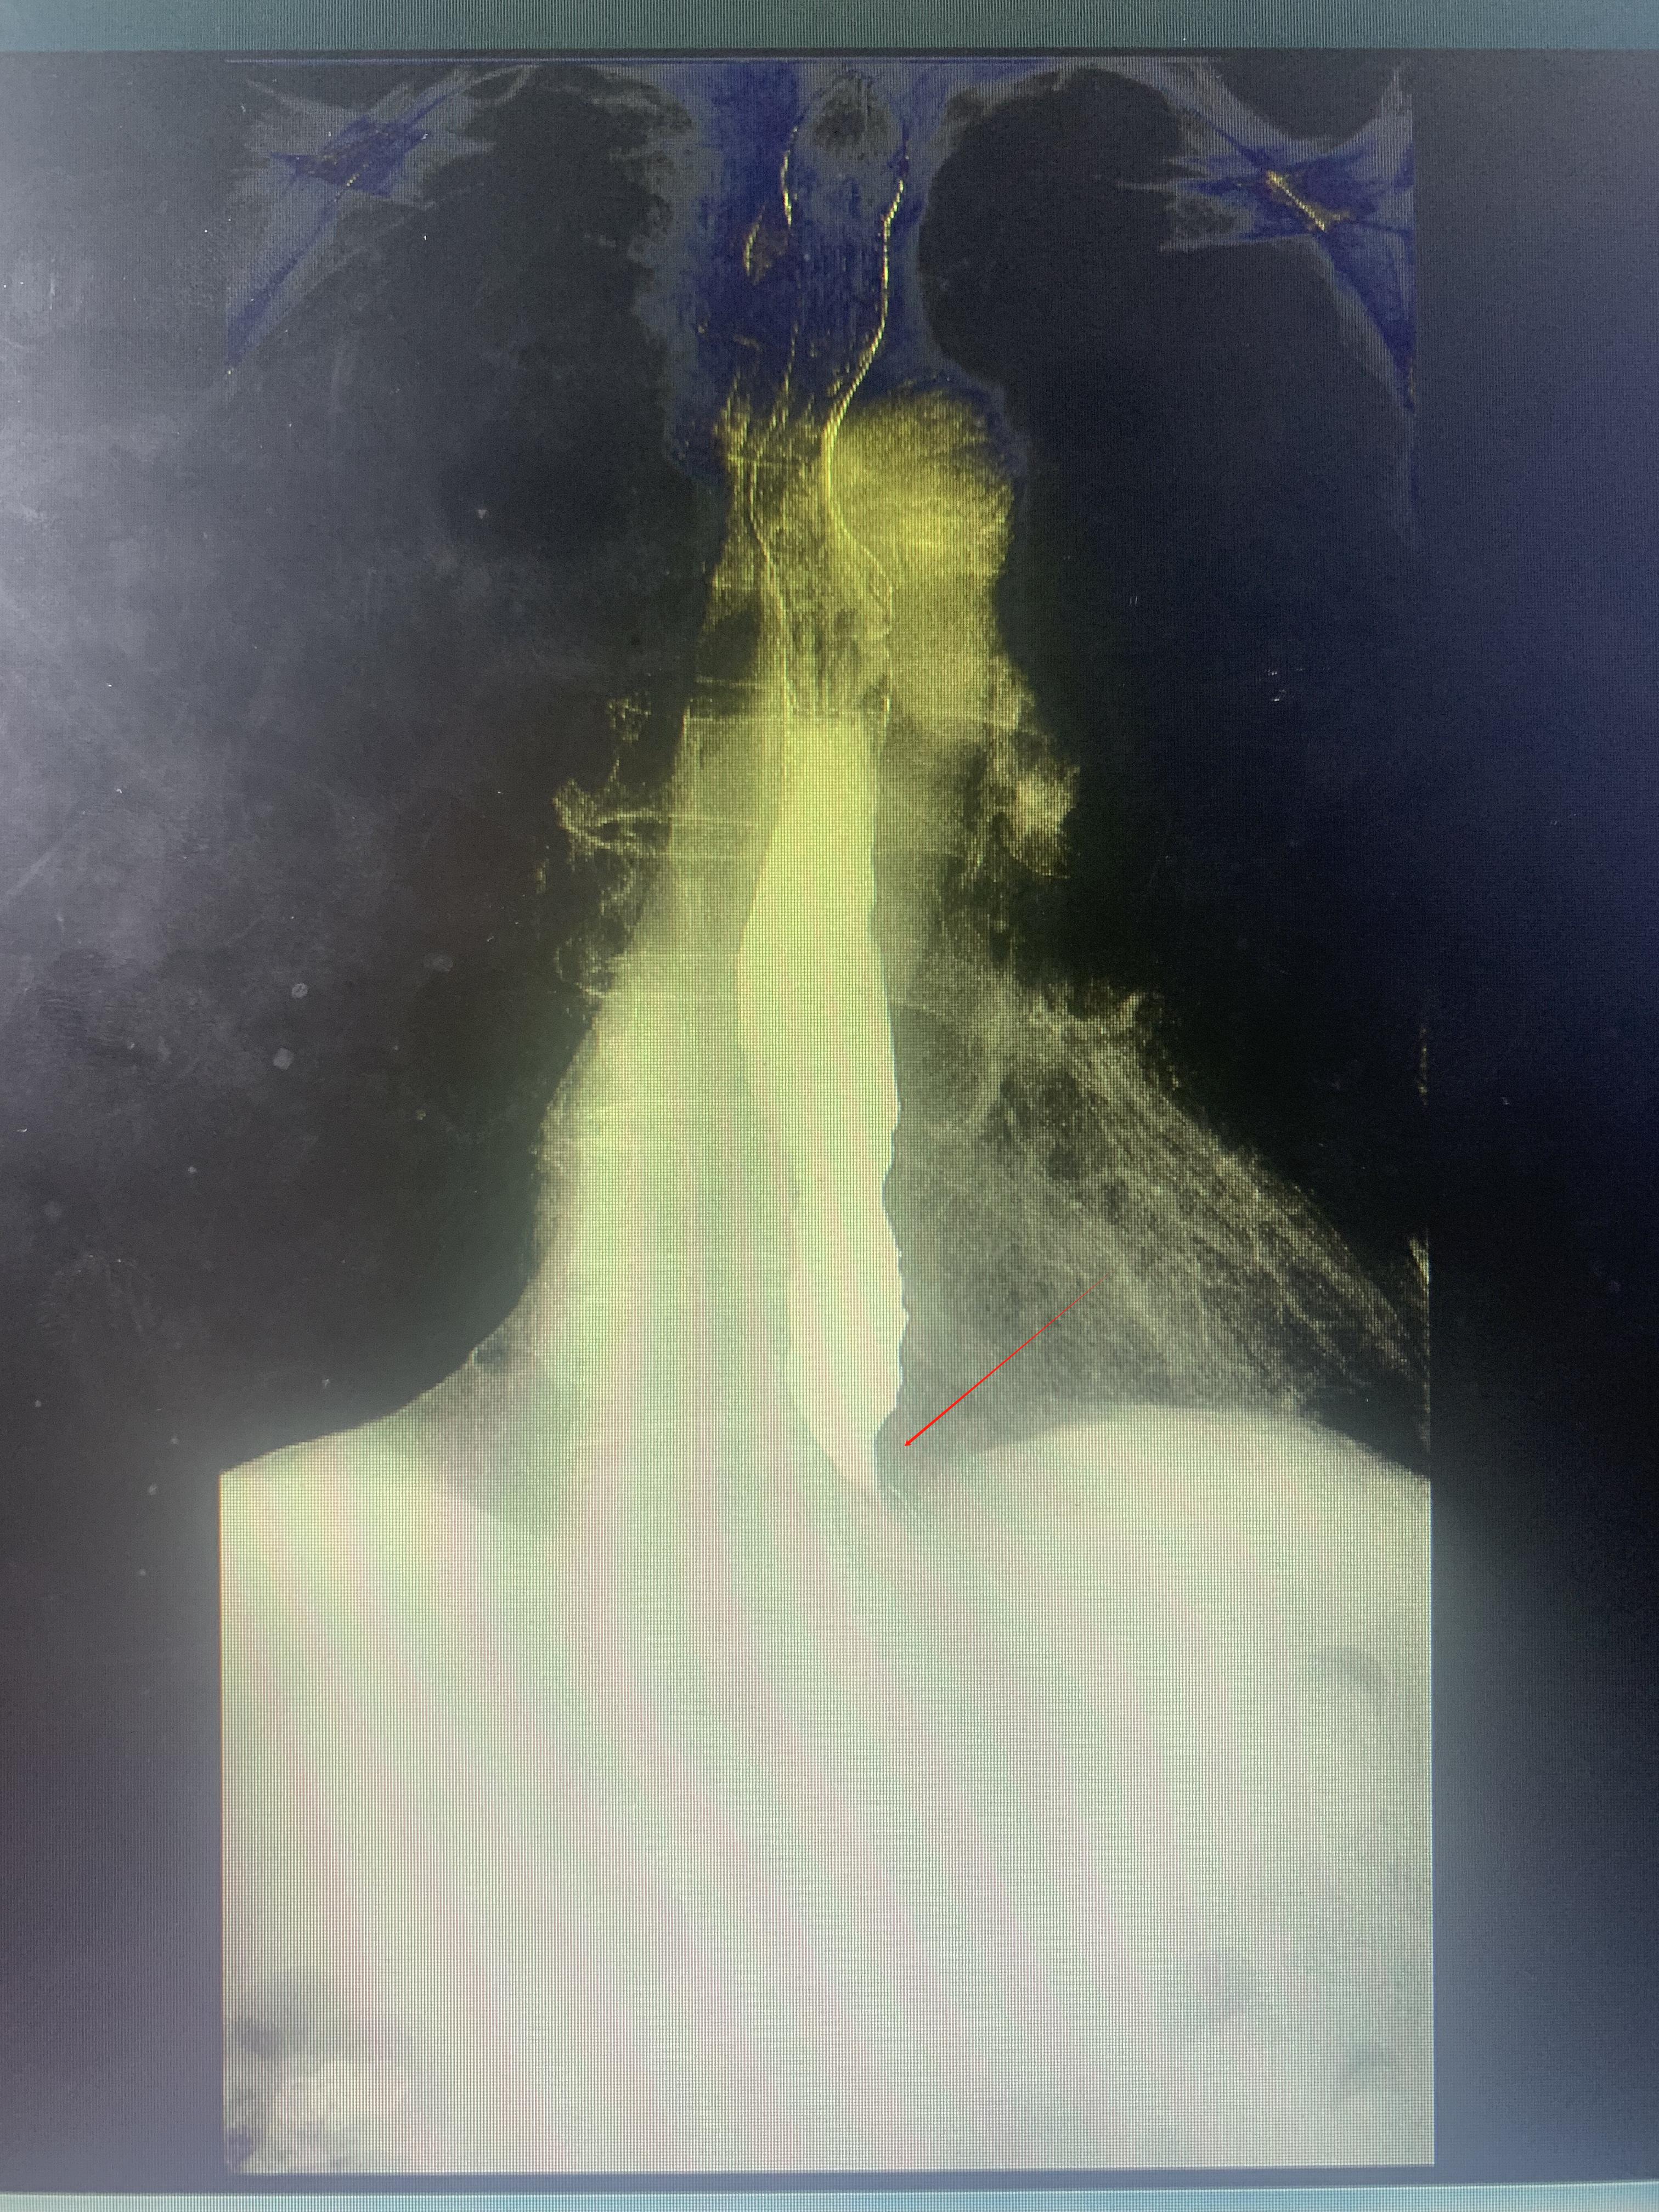

接诊的消化内科主任王新颖发现,陈爷爷的食管造影呈现典型“鸟嘴征”——食管下端狭窄如针孔,上段扩张如气球,确诊为“贲门失弛缓症”。“贲门是食管与胃的‘闸门’,正常进食时可自动松弛。而患者的贲门因异常持续痉挛,如同被‘紧箍咒’锁死,食物长期淤积食管引发呕吐和营养不良。”王新颖解释道。